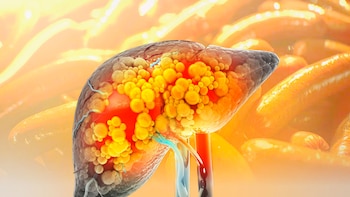

Cuáles son los efectos de comer salchicha, jamón, chorizo y otros embutidos en personas que padecen hígado graso

Estos productos se consumen en diferentes presentaciones y horarios, ya sea en el desayuno, como ingrediente principal de guisos, en tacos, tortas o como botanas